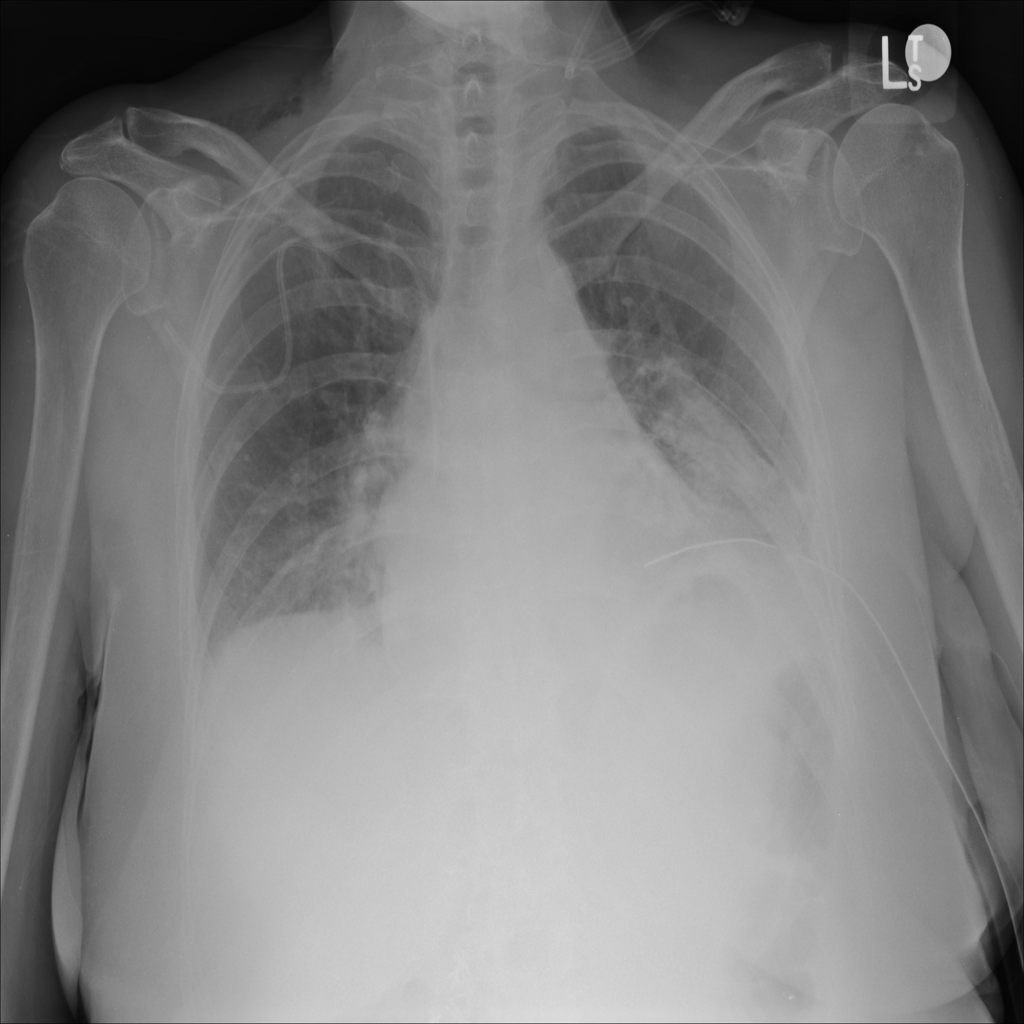

Consolidation

Consolidation refers to air-space filling that makes part of the lung appear denser on imaging.

Showing up to 90 reference images for Consolidation.

PAT-C1A7 · IMG-055Consolidation

PAT-C1A7 · IMG-055

AP